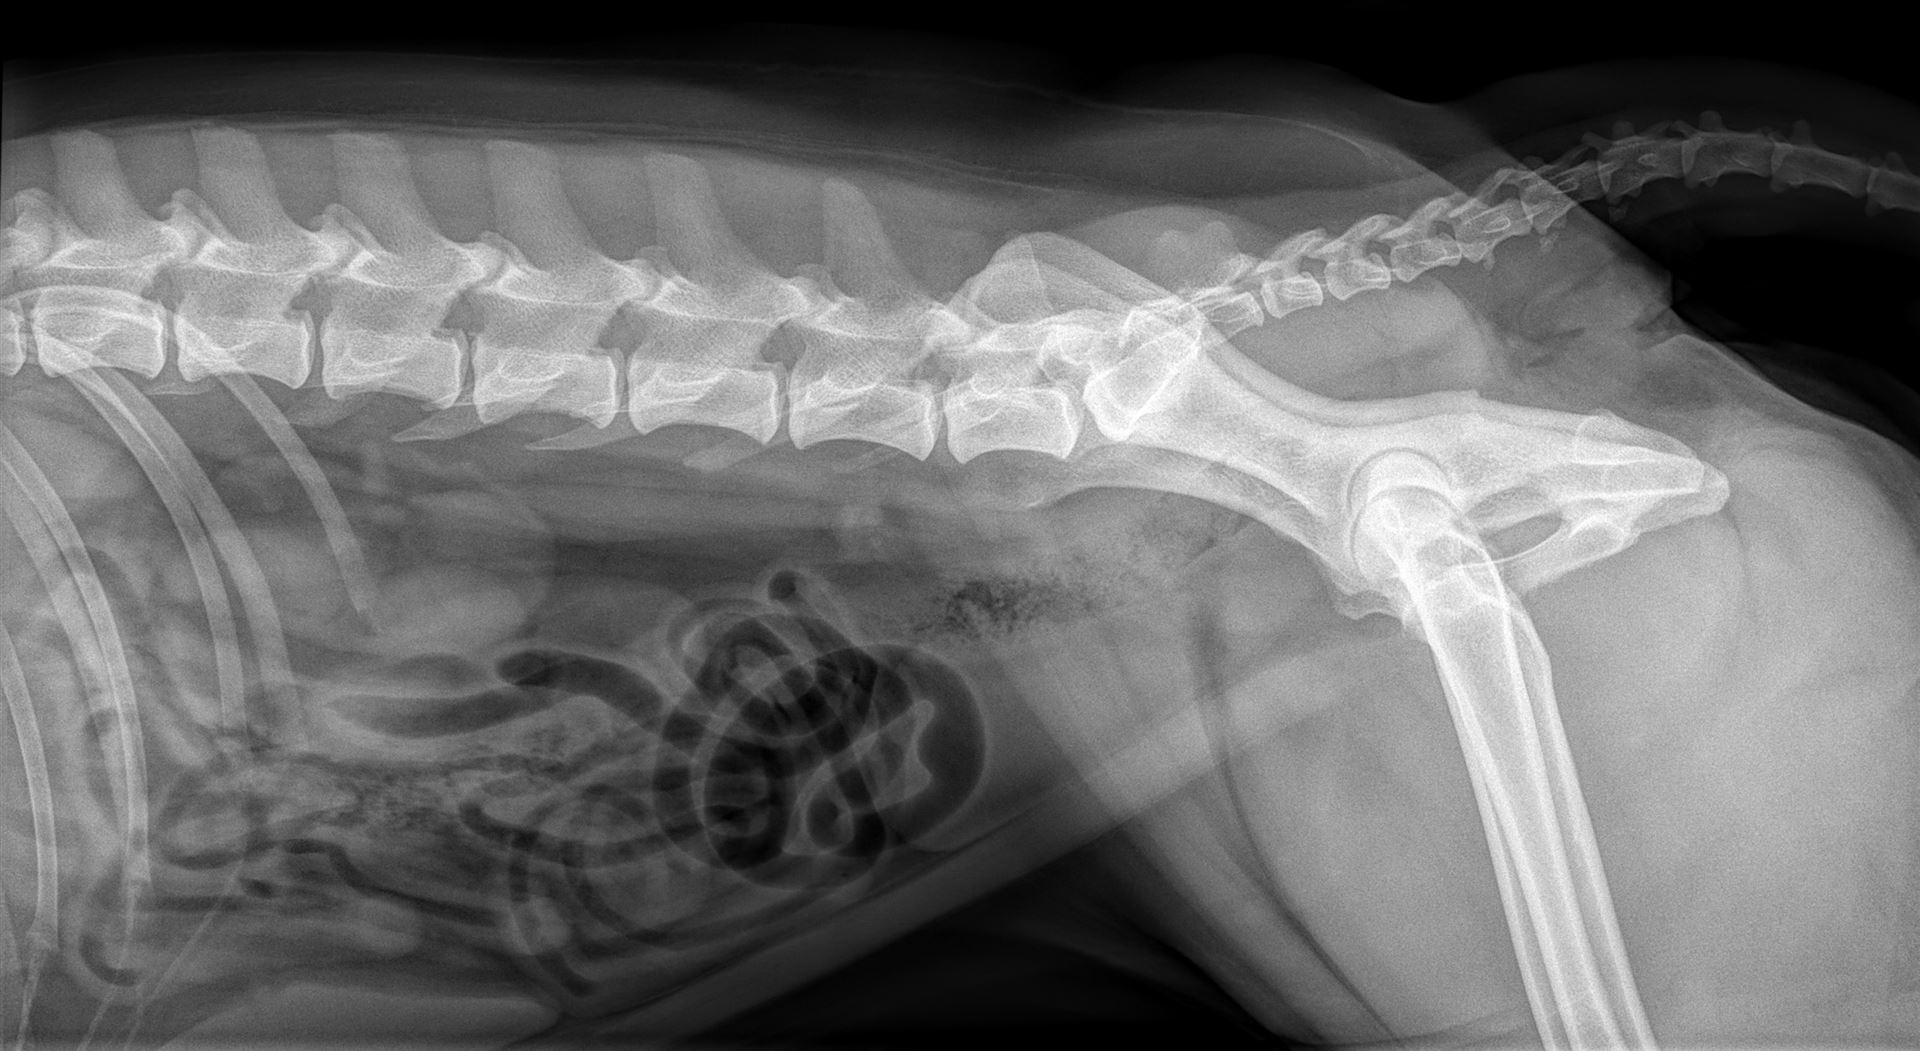

Unsere leistungsfähige Röntgenanlage ermöglicht die Anfertigung qualitativ hochwertiger Aufnahmen von der Katze bis zum Bernhardiner. Röntgenuntersuchungen sind vor allem bei orthopädischen Erkrankungen das Diagnostikum der Wahl, aber auch bei Herz- und Lungenerkrankungen, zur Darstellung von röntgendichten Fremdkörpern und zur Erkennung von Lungentumoren und -metastasen eignet sich die Röntgenuntersuchung hervorragend. Natürlich führen wir auch Zuchttauglichkeitsuntersuchung auf HD, ED und OCD durch.